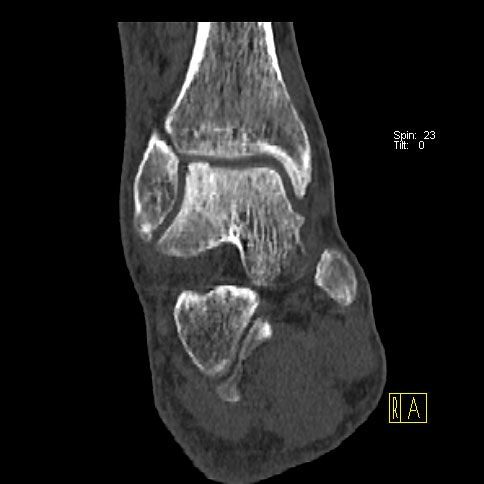

Die Kombination von SPECT und CT in einem Untersuchungsgang bringt wie bereits oben erwähnt eine erhöhte Ortsauflösung und artefaktfreie Darstellung von Knochenstoffwechselveränderungen der SPECT bei gleichzeitig excellent guter anatomischer Darstellung/Zuordnung durch die CT 3. Auf die Vorteile der CT gegenüber dem konventionellen Röntgen muss nicht mehr besonders eingegangen werden. Besonders eignet sich die „SPECT-CT“ zur Diagnostik von Fußerkrankungen (Biersack HJ et al. 2012).

Grundlage der Skelettszintigraphie ist die Verwendung von osteotropen Radiopharmaka, die nach intravenöser Applikation zur Beurteilung der locoregionären Durchblutung (Hyperperfusion) und zur Abklärung des Knochenstoffwechsels verwendet werden. Indikationen zur Skelettszintigraphie sind entzündliche und tumoröse Skeletterkrankungen, Abklärungen von Prothesenlockerungen und in individuellen Einzelfällen auch zur Detektion occulter Frakturen (z.B. bei Kindesmißhandlung) (Schümichen C. 2006), (Schümichen C., et al. 2006). Dabei wird je nach Fragestellung ein statisches und/oder dynamisches Untersuchungsprotokoll durchgeführt, z.B. eine statische Skelettszintigraphie zur Verlaufsbeurteilung von bekannten ossären Metatasen oder eine 3-Phasen-Skelett-Szintigraphie bei Verdacht auf eine Prothesenlockerung. Die zusätzlich zur Szintigraphie angewendete SPECT-Technik (rotierende Gamma-Kamera) erlaubt eine höhere Ortsauflösung sowie eine artefaktfreie Darstellung etwaiger knöcherner oder anderer Läsionen. Im Vergleich zur CT ist die Strahlenbelastung gering (Schümichen C. 2006).